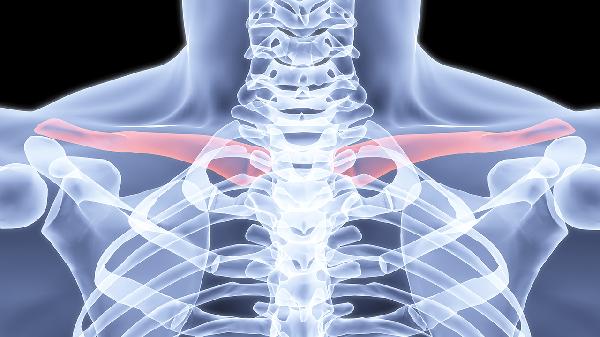

锁骨骨折错位多数情况下可以保守治疗。治疗方案选择主要取决于骨折类型、错位程度、患者年龄等因素,常见处理方式包括八字绷带固定、锁骨带固定、功能锻炼、定期复查及手术评估。

适用于轻度错位的锁骨中段骨折。通过交叉缠绕的绷带限制肩关节活动,利用胸廓支撑力维持骨折端相对稳定。固定期间需每周调整松紧度,避免皮肤压迫或神经损伤,通常需维持4-6周。

针对短斜形或横形骨折伴中度错位。专用锁骨带通过向上提拉肩部实现复位,需配合X光监测复位效果。固定期间需保持直立坐姿睡眠,避免侧卧导致固定失效,儿童患者愈合周期约3-5周。